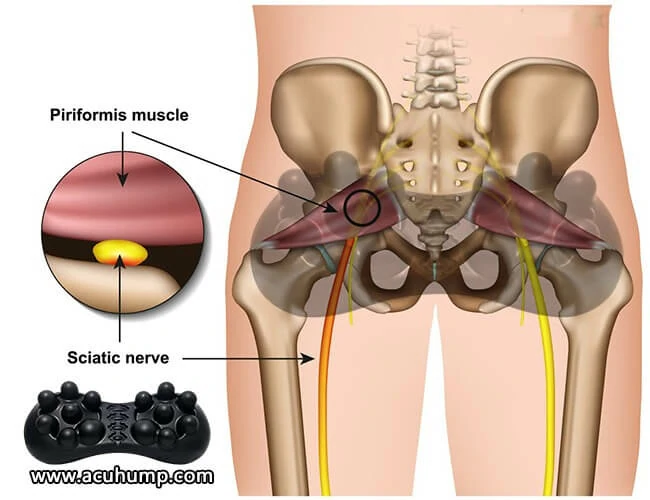

Piriformis syndrome is a condition that affects the piriformis muscle, which is located in the buttock area. This muscle is responsible for stabilizing the hip joint and helping with leg movement. When the piriformis muscle becomes tight, irritated, or damaged, it can cause pain and discomfort in the buttock, as well as down the leg. Early diagnosis and treatment of this condition can prevent further complications.

There are several common causes of piriformis syndrome. One of the primary causes is the tightening of the piriformis muscle, which can result from overuse or lack of stretching. Additionally, the piriformis muscle may become irritated or damaged, leading to the development of this condition.

Acu-hump is an incredibly effective tool for massaging and stretching the piriformis muscle. This muscle is located deep in the buttock area and can become tight and inflamed, leading to pain and discomfort. By incorporating Acu-hump into your daily routine, you can help to release tension in the piriformis muscle and promote overall relaxation in the lower body.

Using Acu-hump to massage the piriformis muscle is simple and effective. Simply place the tool under the affected area and use it to apply pressure to the muscle. You can adjust the pressure to your liking and focus on areas that feel particularly tight or painful. The raised bumps on the tool will work to target and release pressure in the muscle, promoting relaxation and pain relief.

In addition to massage, stretching with Acu-hump can also be incredibly effective for releasing tension in the piriformis muscle. By using the tool to support and extend the muscle, you can work to increase flexibility and reduce the likelihood of injury. Regular stretching exercises can help to prevent the development of piriformis syndrome, while also promoting overall health and well-being.